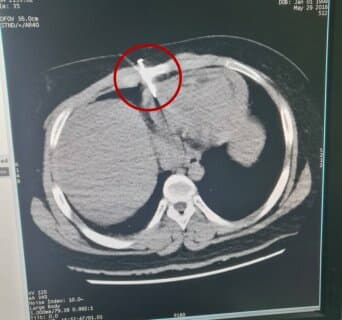

徐州医科大学附属第三医院胸心外科,每年都要接诊近百例食管气管瘘患者,据沙主任介绍,食管内置支架主要适用于中晚期恶性食管疾病患者,及一些年龄较大、不适合手术或者身体情况不好,不宜化疗的病人。通过在食管内放置支架的方法,可快速解除狭窄或梗阻,恢复患者进食功能,有效改善患者生活质量,帮助病人赢得更多的治疗机会和生存时间。

二十几年来,徐州医科大学附属三院胸心外科,像这样的食管支架手术已完成了4000多例,莎氏扩张术已成功完成食管良恶性狭窄10000余例次,均取得了良好的临床治疗效果和良好的社会效益。